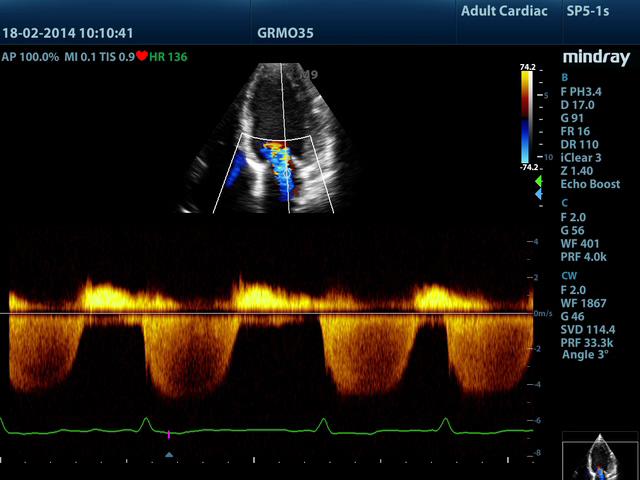

CW – режим постоянно-волнового допплера (непрерывноволновой допплер)

Постоянно-волновой допплер (continuous wave Doppler – CW) в истории допплеровской эхографии является первым используемым методом. Для использования данного режима применяются специализированные датчики: двухэлементные CW-датчики карандашного типа (pencil probe) и дуплесные датчики, которые могут работать в B-режиме.

Режим CW, в силу физических принципов работы, не имеет ограничений по скорости и глубине, но, в тоже время, он не имеет и пространственного разрешения. Режим CW имеет особую ценность при исследованиях высокоскоростных потоков в области стенозов артерий, артериовенозных шунтов, исследованиях сердца.

ff41e97b5f8138f7a125560a2fe53d1c60e233d4.jpg